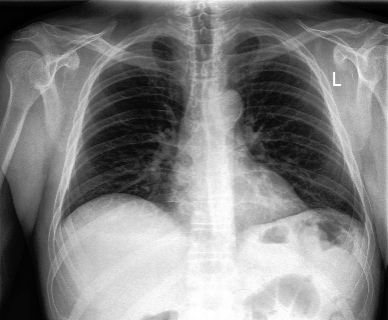

Qualitatively, Fig. 5 shows a significant improvement of the visual realism across all methods when using a drift of . The background is consistently black as in real brain MR images; the shape of the brain becomes more realistic, and the white and gray matter structure improves. For an analytical evaluation, we calculated the FID between our test data and 200 synthetically generated images from each method (100 CN, 100 AD). The results in Tab. 1 demonstrate that LD improves the ability of the model to generate realistic MRI slices for both healthy brains and brains with Alzheimer’s disease. For this reason, all following experiments were done with LD.

We use the Pix2Pix Zero model with a basic fine-tuned Stable Diffusion model to generate healthy brain MRIs from ones diagnosed with Alzheimer’s Disease and vice versa. We generate the counterfactual images by negating the ground truth label of the 200 test samples and conditioning the model on the negated label value and the source image. We compute image quality metrics, as well as the AUC, using a disease classification model trained on 600 real brain MRI slices (300 AD, 300 CN). Additionally, we determine the Structure Similarity Inced (SSIM) between the target and the source image to determine how well the identity of the source image is retained. The qualitative results in Fig. 6 , illustrate four examples from our two editing directions: from AD to CN and from CN to AD, respectively. When transitioning from AD to CN, the model primarily reduces the size of the ventricles. Conversely, in the CN to AD transformation, the ventricle size increases, accompanied by a worsening of brain atrophy.